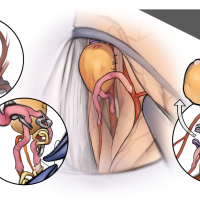

OPExPARK20220412コンテンツシリーズ

OPExPARK20220405コンテンツシリーズ

OPExPARK20220130コンテンツシリーズ

OPExPARK20220518コンテンツシリーズ

OPExPARK20220323コンテンツシリーズ

OPExPARK 2021013コンテンツシリーズ

OPExPARK 0915コンテンツシリーズ